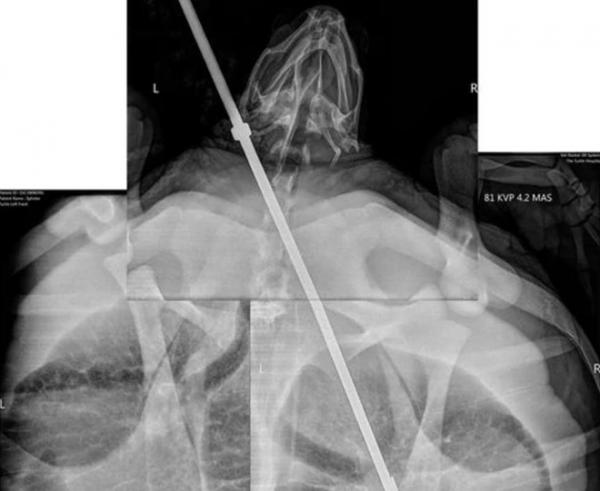

Sau khi chụp X-quang, các bác sĩ phát hiện thanh kim loại 3 cánh găm sâu vào đến nửa người con rùa.

Hình chụp X-quang cho thấy ngọn giáo trong cơ th.ể con rùa. Ảnh: Washington Post.